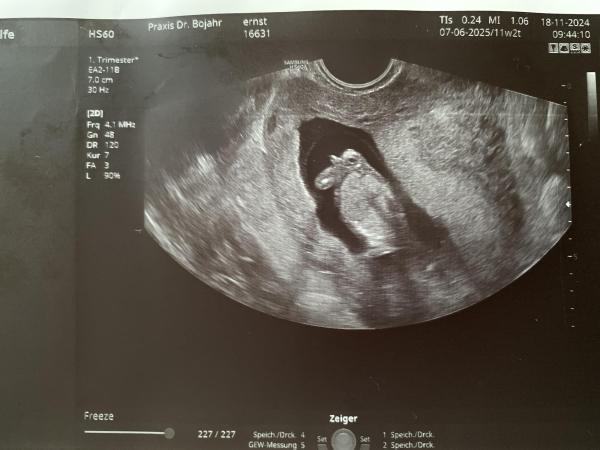

Hallo Ihr Lieben da draußen, ich war gestern in der 12 Ssw bei dem ersten großen Ultraschall und habe dieses Ultraschallbild bekommen. Der Arzt wollte zum Geschlecht noch nichts sagen und ließ mich im Dunkeln. Deswegen meine Frage an Euch: Kann irgendwer diese Ultraschallbild hinsichtlich des Geschlechted deuten?   LG an Alle

Bild zu Ultraschall Geschlechter Erkennung? - Forum für Juni - Mamis

Guten Morgen,  leider kann ich dir zu deinem Bild nichts sagen außer dass ich ein niedliches Häschen 🐰 sehe ☺️  Soweit ich weiß dürfen die Ärzte so früh auch noch nichts zum Geschlecht sagen. Meine frühestens ab der 14. Woche (bin mir aber nicht ganz sicher) Vielleicht möchtest du dich ja auch noch in die Kugelliste mit eintragen?

Bis zur 14 SSW sehen die Geschlechter identisch aus und haben nur winzige Unterschiede

Der Arzt darf so früh noch nichts sagen, selbst wenn er könnte. So früh kann man die Geschlechter aber ohnehin nicht (zuverlässig) unterscheiden. Daher seh ich es auf dem Bild auch nicht.